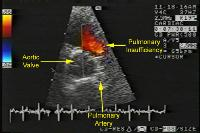

3)

Echocardiogram show right ventricular wall thickening (RVH)

and paradoxically septal (IVS) motion during systole, and the

site of obstruction. Doppler studies can assess the degree of

stenosis.

Fig1: Normal echocardiographic parasternal cross sectional

view of pulmonary valve.

Fig2: Doppler study of case of severe pulmonary stenosis with

a Doppler velocity of 5.22m/sec.(pulmonary gradient of 109mmHg.

Fig3 Echocardiogram,parasternal ,cross sectional view of a

case of pulmonary stenosis with marked regurgitation